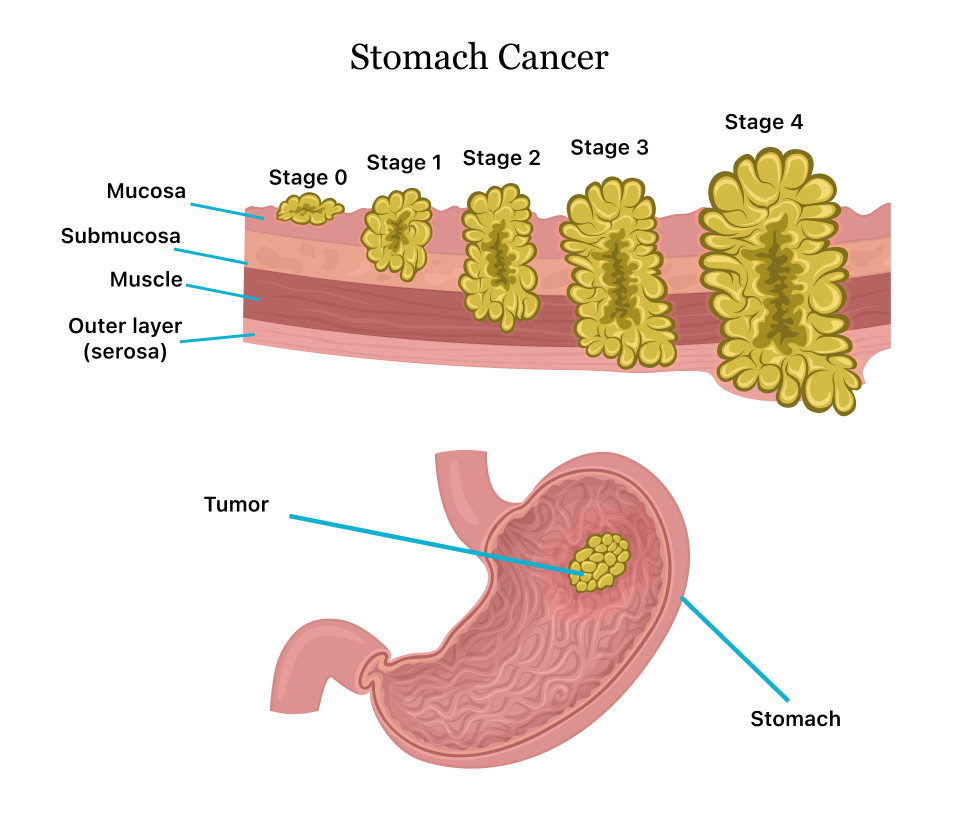

Stages of stomach cancer Royalty Free Vector Image

Stomach Cancer. Vector Illustration for Medical Use Stock Vector …

Stages Of Gastrointestinal Cancer | herxheim.de